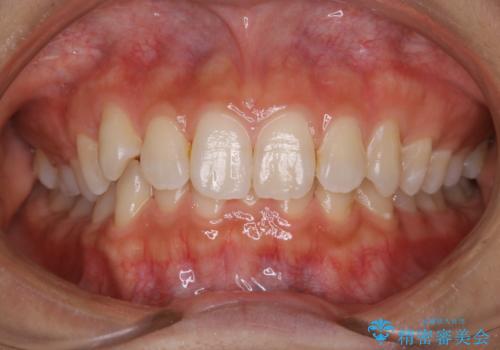

- 矯正治療を始める前に、歯のクリーニング希望とのことでした。

PMTC30分コースを行いました。

PMTCを行うことにより、スッキリと爽快感が得られたり、見た目も清潔感のある状態になるため、今後の治療などお口に対するモチベーションUPにも繋がります。